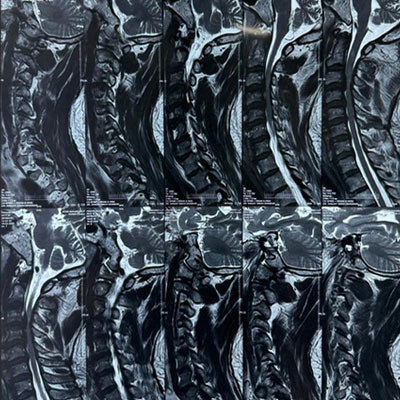

Surgical Highlights